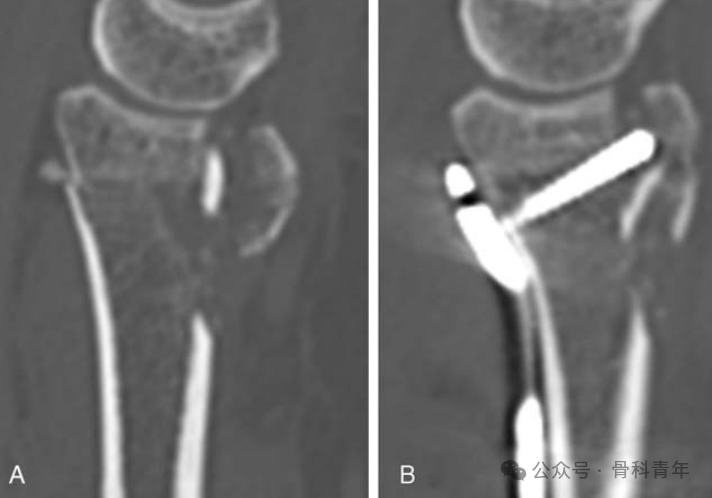

▲ 图示在背侧骨块的固定上,掌侧螺钉存在劣势。